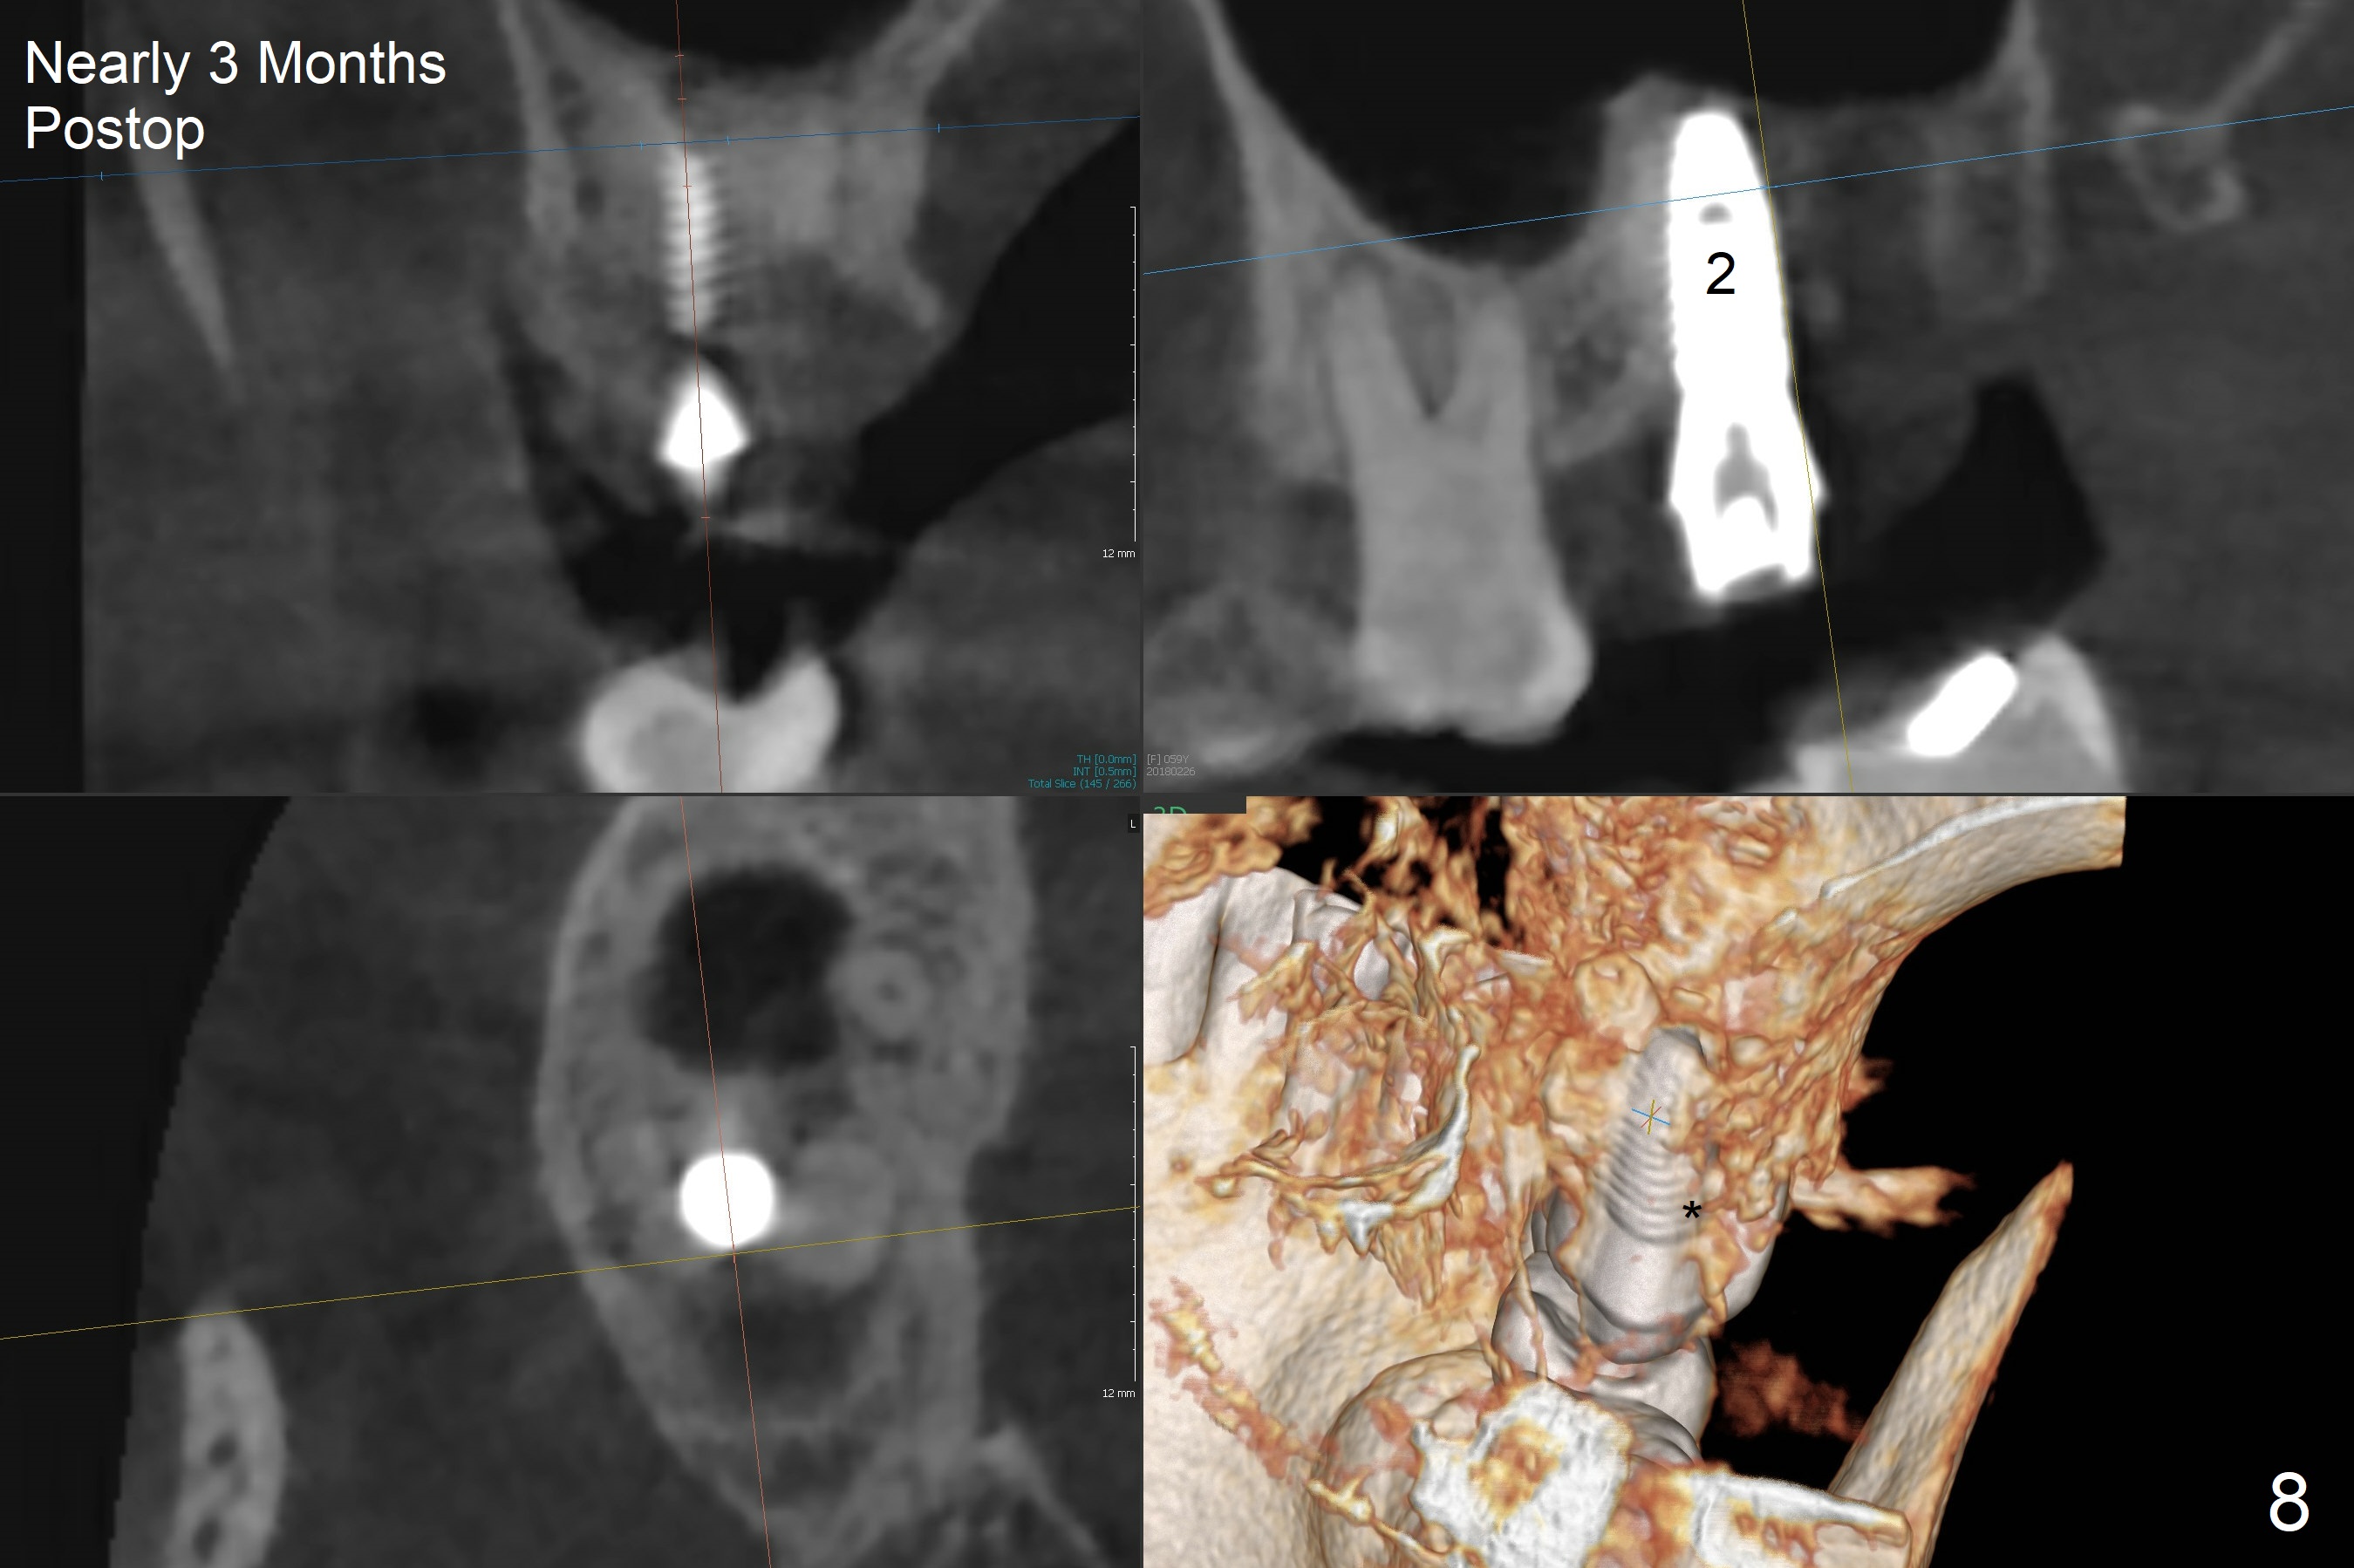

After extraction of the 3rd molar with mesial periodontal defect, osteotomy for 2nd molar implant is initiated in the mesial slope of the 3rd molar socket (Fig.1 red dashed line). When osteotomy is finished with IS drills and sinus lift with Magic Sinus Lifter (S-reamer with 11 mm stopper being short), a 4x10 mm dummy implant is placed with ~ 4 implant thread exposure (Fig.3). Following use of Lindamann bur to move osteotomy mesial and larger drill, a 4.5x10 mm implant is placed with 5-7 implant threads exposed distally (Fig.4,7 (~ 50 Ncm)). The bucco(B)-palatal(P) extent of the implant thread exposure is larger (Fig.5) than that associated with the 4 mm dummy implant (data not shown). The exposed implant surface is covered with Vera Graft (Fig.7*), Collagen plug and an immediate provisional after adjustment of abutment height (Fig.6,7). The bone density distal to the implant is low 3 months postop (Fig.8,9 CBCT) and 3.5 months postop (Fig.10,11). The permanent crown is cemented nearly 4 months postop. The distal cortical bone contacts the implant (Fig.12 ^), while the mesial bone increases in density (*) 2 years postop.